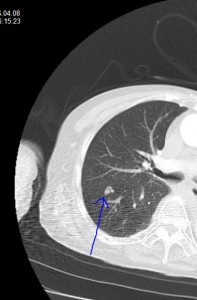

「肺動脈静脈瘻」について学びました。

肺炎も肺梗塞もないのに、著明な低酸素血症を呈します。

CT画像ではあまり目立たないクリっとしたコイルのような血管がみえます。血液ガスではシャントが存在するので、PO2、PCO2ともに低下します(A-aDO2が開大します)